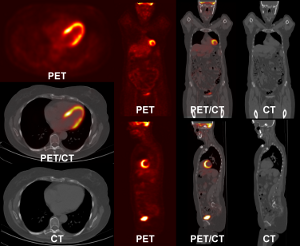

Figure 2: Schema of a PET acquisition process.

Figure 2 illustrate the PET acquisition process. After interactions, a positron combines with an electron. It generally produces two photons of 511 keV emitted in opposite directions. They are detected in ‘coincidence’ (i.e. almost at the same time). The line between the detectors that have been activated for a given pair of photons is called line of response (LOR).